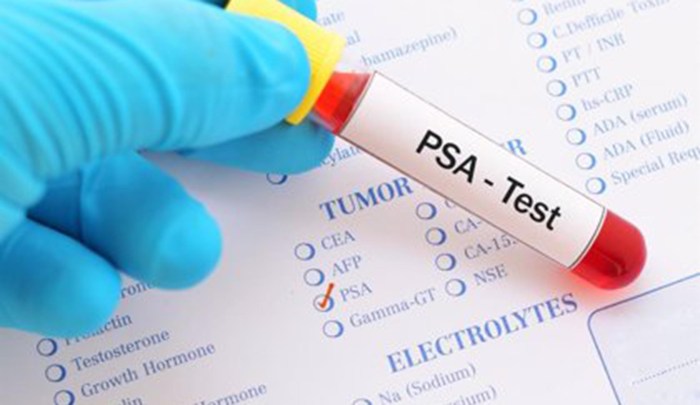

Los niveles de PSA tras el tratamiento pueden no ser un indicador fiable de la supervivencia en cáncer de próstata

Un estudio dirigido por la Universidad de California Los Ángeles (UCLA) ha descubierto que los tratamientos que reducen el riesgo de que se diagnostique una recidiva del cáncer en función del aumento de los niveles de antígeno prostático específico (PSA) tras la radioterapia, lo que se conoce como recidiva bioquímica, no mejoran necesariamente la supervivencia … Continuar leyendo Los niveles de PSA tras el tratamiento pueden no ser un indicador fiable de la supervivencia en cáncer de próstata